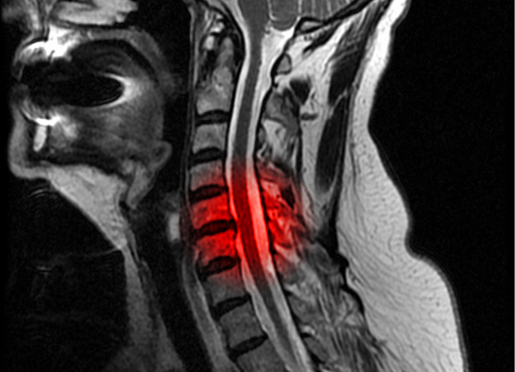

Originally described in the Japanese population, where it affects approximately 4-5% of the population, OPLL is seen in approximately 1.5% of the U.S. population. It most commonly becomes symptomatic in those 40-70 years of age, presenting as a progressive myelopathy. OPLL is more common in the cervical spine than either the thoracic or lumbar segments, although the entire spine may be involved. Presenting symptoms include progressive gait difficult, coordination problems of the hands associated with burning upper extremity pain, as well as upper extremity radicular pain, weakness and numbness. Diagnosis is based on MRI to determine the degree of cord compression as well as to identify the number of levels involved; CT of the cervical spine is indicated as well to confirm signal changes associated with the presence of the abnormal bone anterior to the cord as well as to determine the “occupation ratio.” (See below.)

Unfortunately, if presenting symptoms show myelopathic features, progression is common and operative decompression is indicated. The Occupation Ratio refers to a measure on CT of the anterior-posterior distance of the spinal canal occupied by the abnormal bone divided by the expected normal anterior-posterior distance of the canal at this level. An occupational ratio of 30-60% predicts the development of myelopathy, while a ratio of greater than 60% requires immediate surgical decompression in almost all patients healthy enough to tolerate the surgery.

The following case study illustrates the complexity of a patient with multi-level continuous cervical OPLL presenting with a progressively severe cervical myelopathy and a high occupation ratio requiring anterior-posterior surgery.